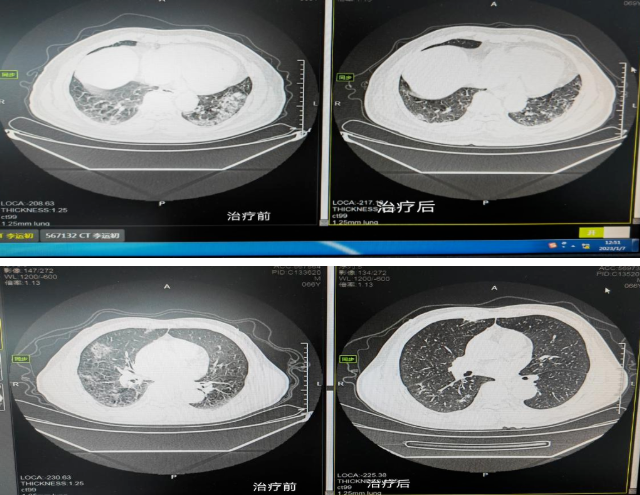

“我的命是这里的医生和护士救回来的,要不是他们,我可能就没命了!”2023年1月12日,在我院骨伤三科病房,今年76岁的赵娭毑眼含热泪说道。赵娭毑因感染新冠,发展为重症“白肺”,在历经2次插管、1次心脏骤停后,终...